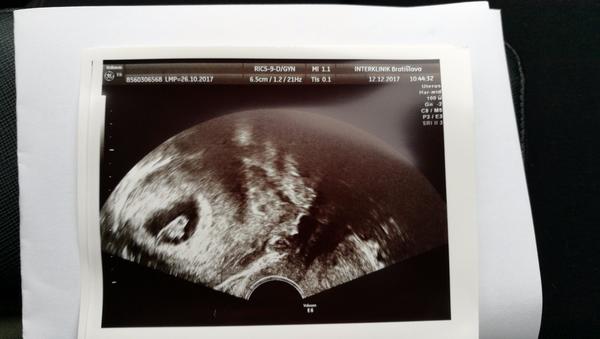

@sangre jeeej gratulujem a drzim silno palce!:* v ktorom tt si, ze je to uz tak pekne vidno?